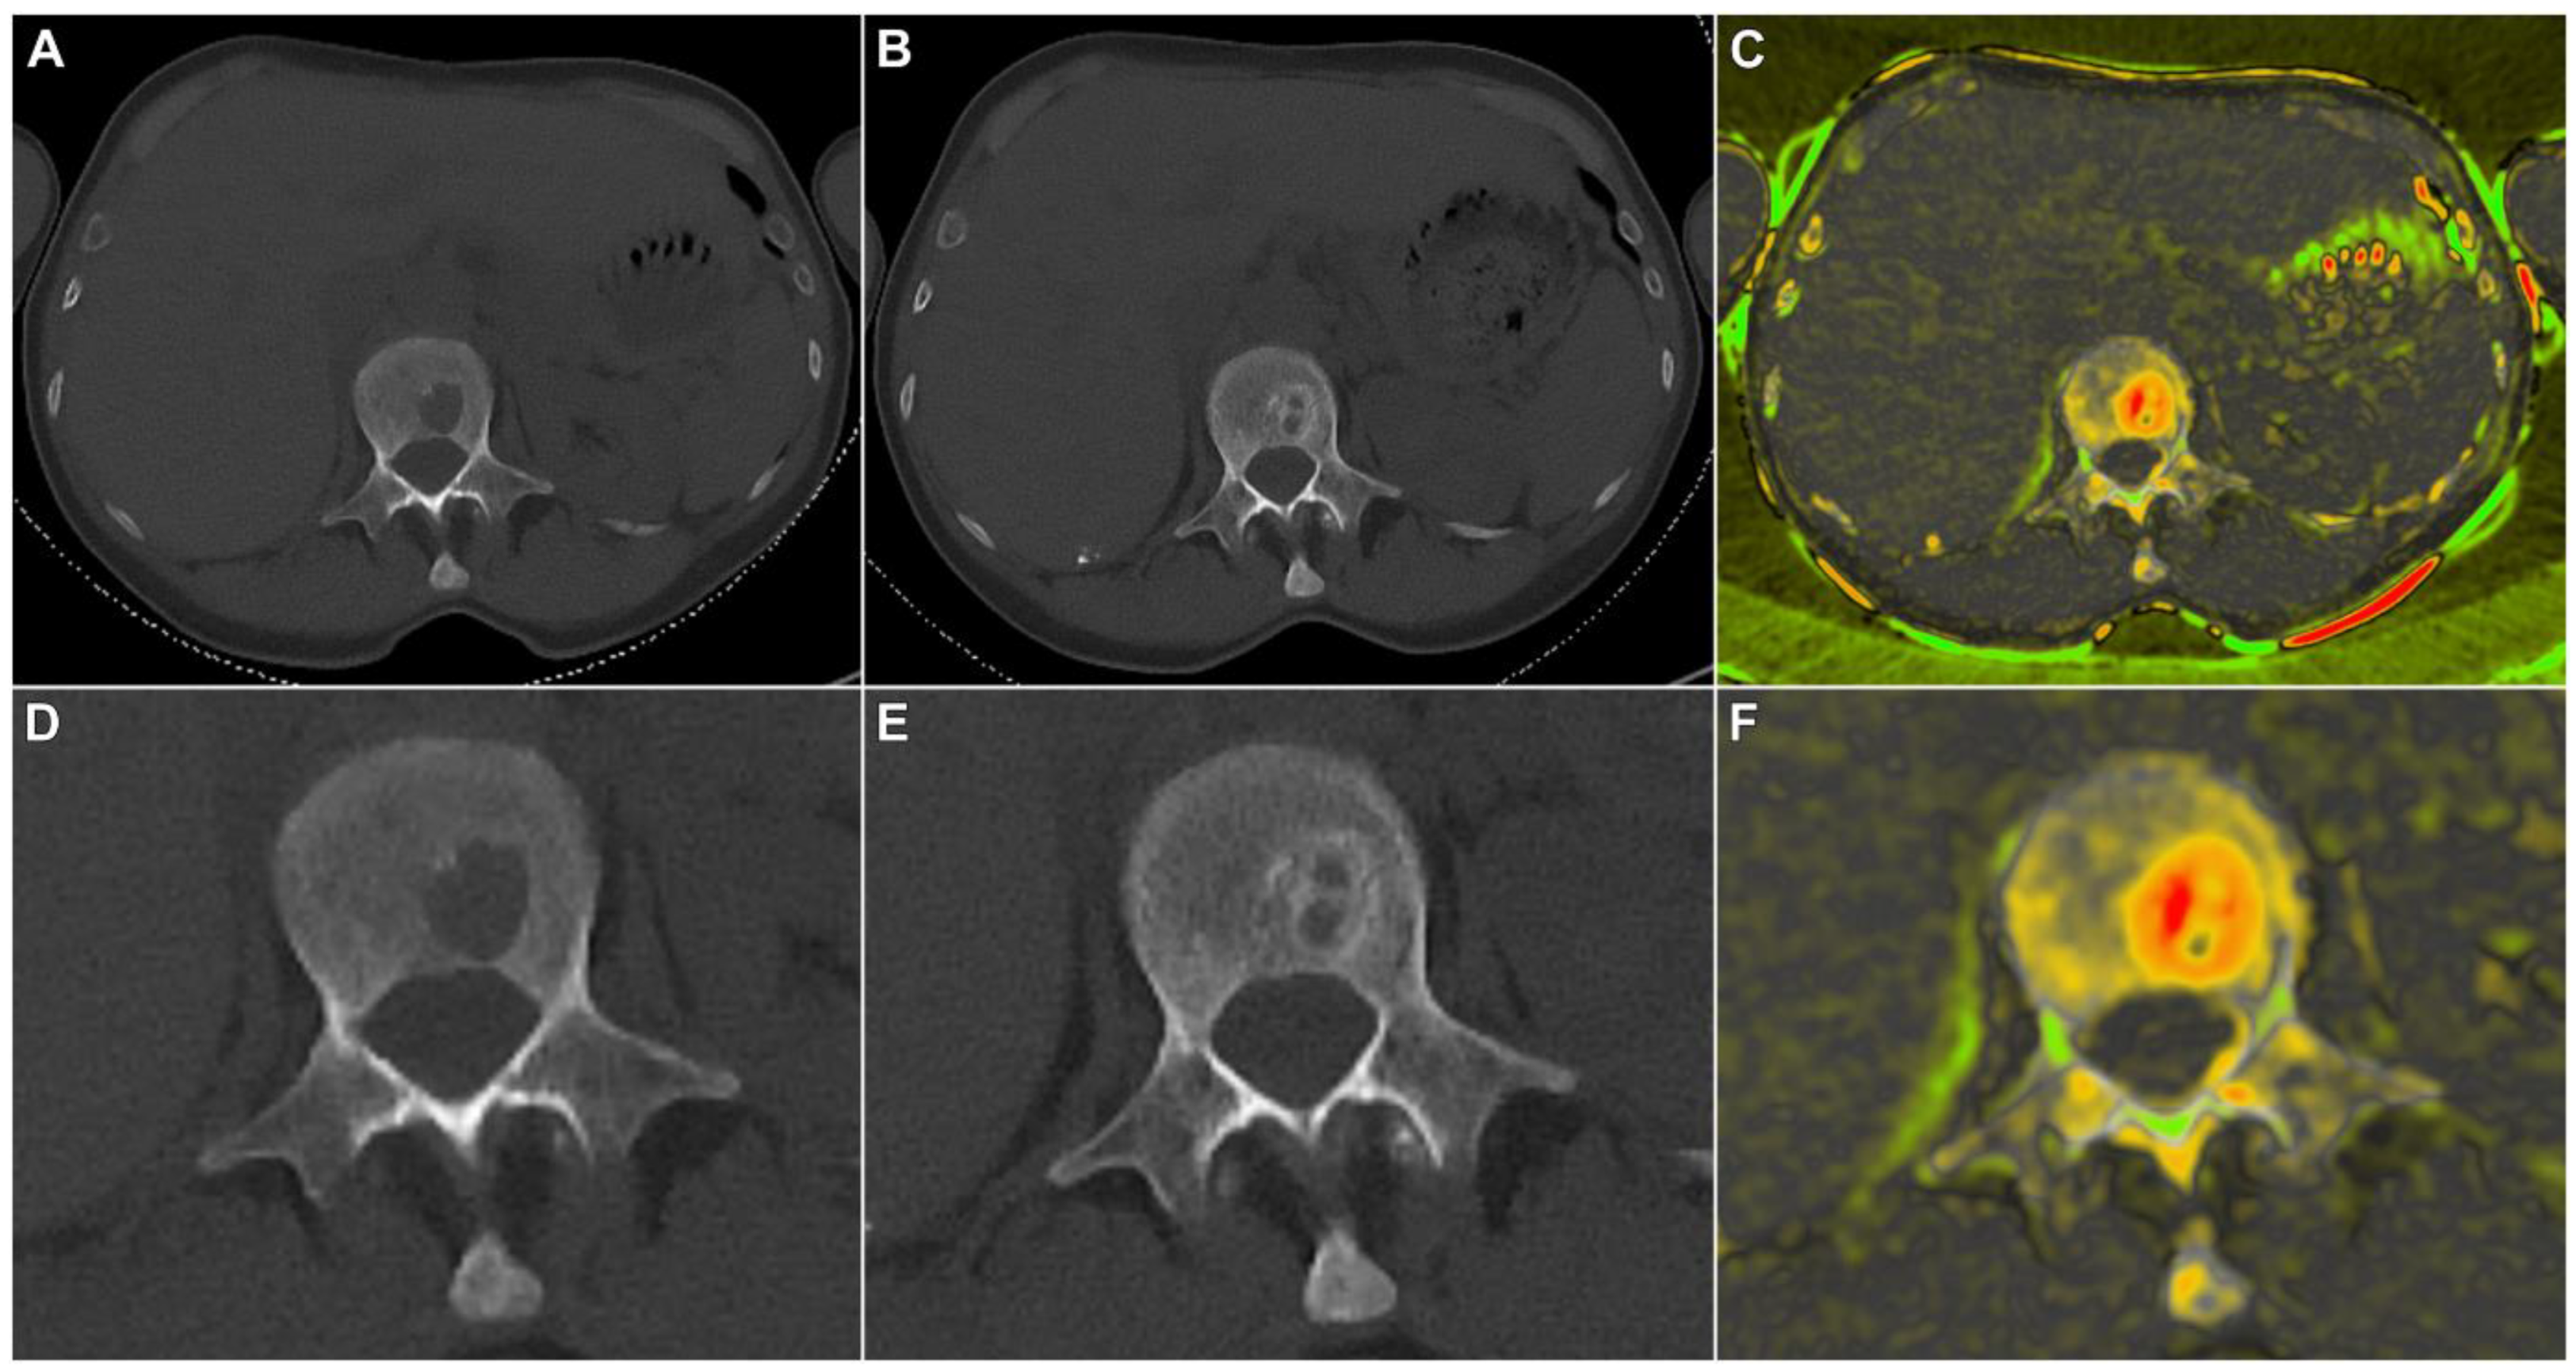

3.2. Quantitative Lesion Characterization before and after Induction Therapy

3.3. Qualitative Criteria of Therapy Response